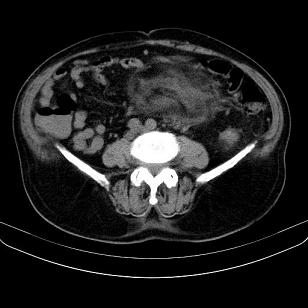

支持;后腹膜脂肪肉瘤诊断。

另肠腔扩张及液平,肠梗阻?